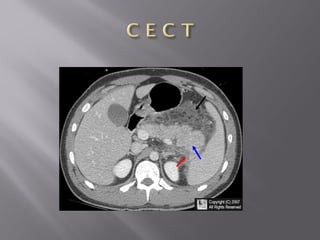

 It isa very common condition in older patients.  Diverticula- A characteristic muscle abnormality in the sigmoid colon with typical ‘out pouching’ from the colonic wall  Diverticulosis - presence of diverticula, Diverticulitis – refers to inflammatory changes within one or more diverticula

• 35.

U S Gand CT show diverticulosis with segmental colonic wall thickening and inflammatory changes in the fat surrounding a diverticulum Complications of Diverticulitis such as abscess formation or perforation, can best be excluded with CT.